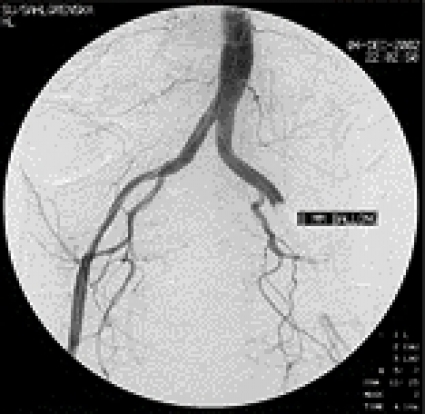

En 5 F införingshylsa infördes i höger femoralartär. Blödningen förmodades härstamma från någon av tarm- eller bäckenkärlen, och initialt gjordes selektiva kateteriseringsförsök. För att påvisa pågående blödning deflaterades aortaballongen från vänster sida. Då profus blödning per rectum åter uppstod utfördes i stället en oselektiv bäckenangiografi, med en kateter placerad distalt i bukaorta. En fistel mellan vänster arteria iliaca externa och rektum påvisades (Figur 2), med en kraftig extravasering av kontrastvätska ut i rektum (Figur 3). En 8 ¥ 30 mm ballongkateter expanderades i arteria iliaca externa över fistelmynningen. Förnyad bäckenangiografi visade upphävd blödning (Figur 4).